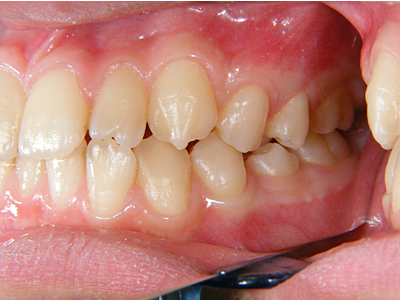

1. 術前正面

この患者様は幼児期から私が拝見している女の子の患者様です。乳歯交換期を終える段階の正面観です。上顎左右3,3番(犬歯)右上1番の中切歯の捻転が著明です。下顎に関しては、右下1番の舌側転位。左下2,3番間の叢生が著明です。正中もそれなりにずれています。

4. 術前右側

下顎前突とまでは言えませんが、上顎が明らかに下顎と比較して劣成長です。年齢的にも上顎の成長はほぼ終了し、下顎の成長は継続しますので、より顕著となり、本当に下顎前突になると考えられます。